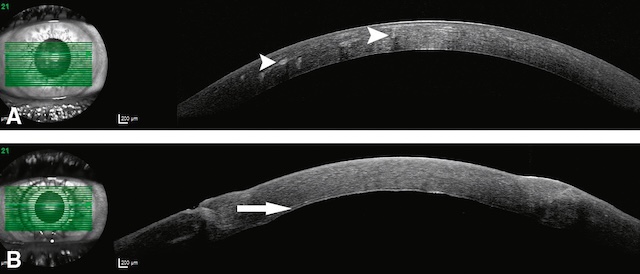

Fig. 10.4 A, B. Images OCT d’une cornée avec des opacités centrales profondes (têtes de flèche), greffée avec une kératoplastie lamellaire antérieure profonde (B) dont on devine l’interface lamellaire (flèche) avec en supérieur le greffon et en inférieur la couche endothélio-descemétique restante du patient. L’image présente deux coupes en OCT de cornée. En haut, la cornée montre des opacités centrales profondes visibles sous forme de zones hyperréflectives localisées (têtes de flèche), traduisant une altération stromale importante. En bas, l’image correspond à une cornée greffée par kératoplastie lamellaire antérieure profonde. On distingue clairement une ligne d’interface lamellaire (grande flèche blanche), séparant le greffon situé au-dessus de la couche endothélio-descemétique native située en dessous. La superposition des images en fond d’œil confirme le bon alignement du balayage OCT, centré sur l’axe optique, et met en évidence la bonne intégration du greffon malgré une légère irrégularité du plan d’interface.